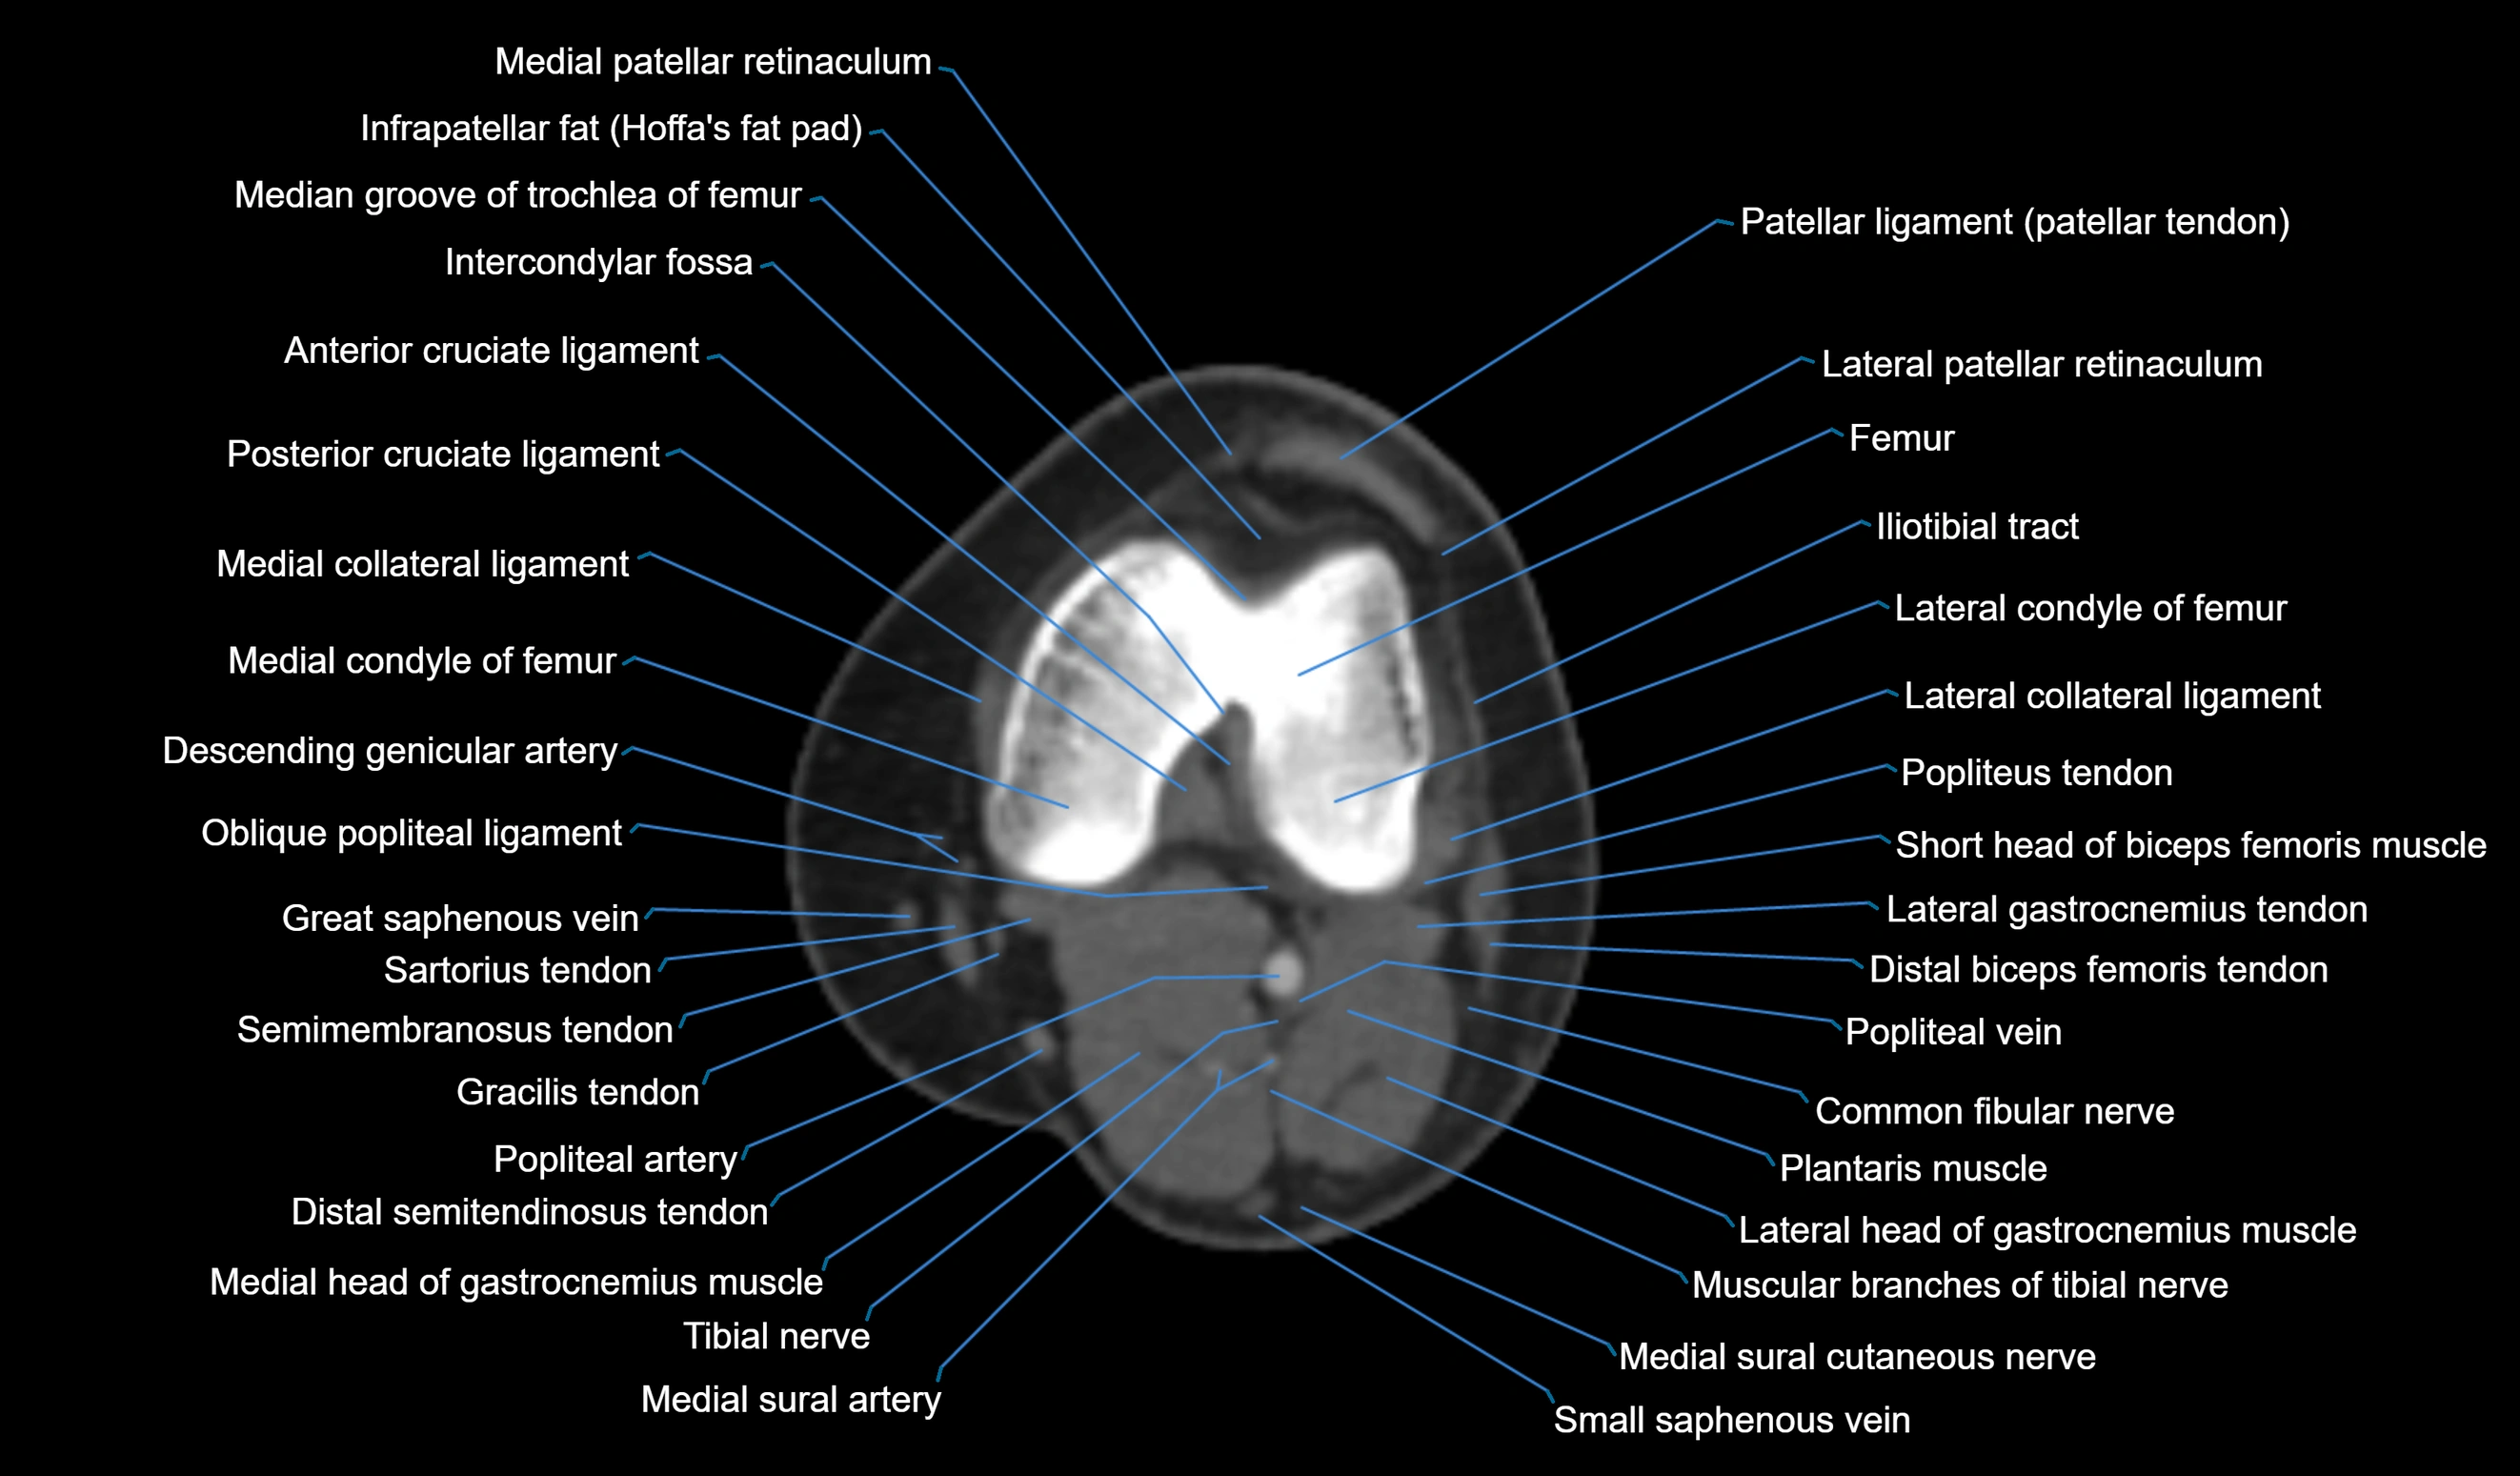

- Anterior cruciate ligament

- Common fibular nerve

- Distal biceps femoris tendon

- Distal semitendinosus tendon

- Gracilis tendon (Distal)

- Lateral collateral ligament

- Lateral condyle of femur

- Lateral gastrocnemius tendon

- Lateral head of gastrocnemius muscle

- Medial collateral ligament

- Medial condyle of femur

- Medial head of gastrocnemius muscle

- Medial patellar retinaculum

- Medial sural cutaneous nerve

- Muscular branches of tibial nerve

- Oblique popliteal ligament

- Plantaris muscle

- Popliteal artery

- Popliteal vein

- Popliteus tendon

- Posterior cruciate ligament

- Small saphenous vein

- Tibial nerve